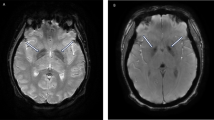

Therapeutic interventions for this condition are broad and have ranged from antipsychotics to immunotherapy [4, 9]. A minority of individuals with DSRD may have a neuroinflammatory etiology to the disease, confirmed by the presence of abnormal neurodiagnostic studies and dramatic immunotherapy responsiveness in some patients [4, 9, 10]. Prior studies have identified that up to 40% of individuals with DSRD have neuroimaging (e.g., T2 signal prolongation or GRE signal abnormalities in the basal ganglia) or cerebrospinal fluid (e.g., pleocytosis, oligoclonal banding, high IgG index, etc.) abnormalities and that when these are present, individuals are more than four times more likely to respond to immunotherapy than other patients [4]. Identification of these findings, which are indicative of neuroinflammation, were a primary rationale for initial studies using immunotherapy in individuals with symptoms of DSRD [4, 10]. While immunotherapy provides a tool to rapidly reverse this clinical syndrome, guidance on dosing and duration of therapy remains unclear.

MRI

All MRIs had to be performed on a 3T scanner with and without contrast administration. Any abnormality beyond a structural malformation (e.g., Chiari malformation) was considered abnormal. Patients did not require a prior “normal” MRI.

With regards to specific neurodiagnostics, patients with EEG abnormality had lower mean for BFCRS and NPITS while on therapy and after therapy relative to baseline. Similar pattern was observed for patients without EEG abnormality while on therapy and after therapy compared to baseline. Patients with abnormal EEG had lower mean NPITS while on therapy (MD: −3.54; 95% CI: −6.04, −1.05) compared to those without EEG abnormality. Patients with abnormal neuroimaging had lower means for BFCRS, CGI-S, and NPITS while on therapy compared to baseline. Similarly, patients without neuroimaging abnormalities had lower BFCRS, CGI-S, and NPITS while on therapy and also after therapy compared to baseline. While patients with abnormal neuroimaging had lower mean for CGI-S while on therapy (MD: −0.69; 95% CI: −1.24, −0.14) compared to those with normal neuroimaging, they had higher means of CGI-S (MD: 1.28; 95% CI: 0.44, 2.12) and NPITS (MD: 5.00; 95% CI: 1.76, 8.24) after therapy compared to patients with normal neuroimaging.